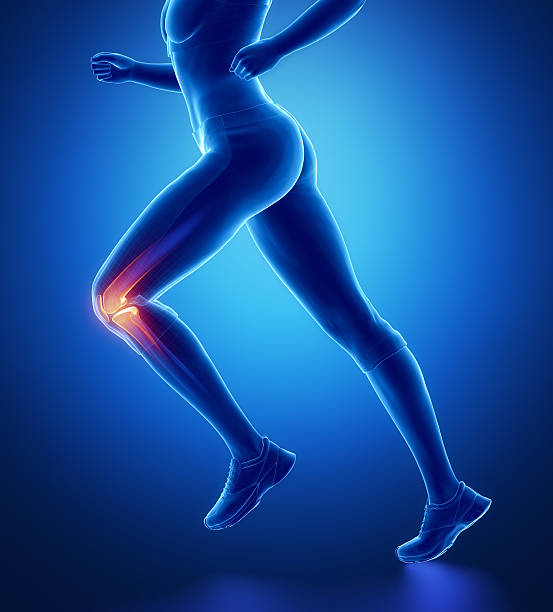

무릎연골은 무릎뼈에 가해지는 충격을 흡수하는 완충장치로 쓰면 쓸수록 닳을 수밖에 없습니다. 이러한 연골은 뼈와 유사한 성분이지만 뼈와 달리 칼슘을 함유하지 않아 뼈처럼 딱딱하지만은 않으며 탄력이 강하고 고무와 유사합니다. 이처럼 연골은 다쳐도 아프지 않기 때문에 치료를 늦추게 되고 병을 키우는 결과가 나올 수 있습니다. 하지만 연골 손상이 더 걱정되는 이유는 연골은 혈관이 없어 한번 손상되면 스스로 치유되거나 재생되지 않는다는 점입니다. 심한 경우에는 손상된 연골이 치유되지 않고 계속 퇴행하며 결국 퇴행성 관절염으로 진행됩니다.

무릎연골은 대퇴골과 경골을 각각 3~4mm 두께로 감싸 관절에 가해지는 충격을 흡수하여 관절이 원활하게 움직일 수 있도록 하기 때문에 심한 충격이나 잘못된 자세로 계속 자극하면 연골이 닳거나 부러질 수 있어 일상 생활에서 관리가 필요할 수 있지만 연골에는 신경이 없어 찢어지거나 닳아도 아프지 않아 연골이 마모되더라도 연골이 아픈 것이 아니라 아래의 뼈가 노출되어 통증을 유발하기 때문에 연골이 손상되었다면 스스로 치유되거나 재생되지 않는다는 점이기 때문에 미리미리 원인을 알고 대비해야합니다.

무릎 연골 손상 증상은 이미 연골이 찢어지고 부러진 경우 통증이 너무 크기 때문에 무릎을 구부리거나 펴거나 제대로 기능하지 못하는 경우가 돼서야 인식하는 경우가 많습니다. 이 경우 연골에 염증이 생기고 증상이 너무 심해 병원에 가서 진찰을 받아야하며 정확한 검사 없이는 정확한 진단이 불가능하고 적절한 치료를 받을 수 없기 때문에 준비를 잘 하셔야 합니다.

무릎 연골 손상은 무릎 관절을 사용하여 움직일 때도 통증을 유발할 수 있습니다. 통증은 무릎 연골의 파열로 인해 발생하는 가장 흔한 통증으로 걷거나 계단을 내려갈 때 또는 내리막길에서 통증을 경험할 수 있어 빠른 치료가 요구됩니다.